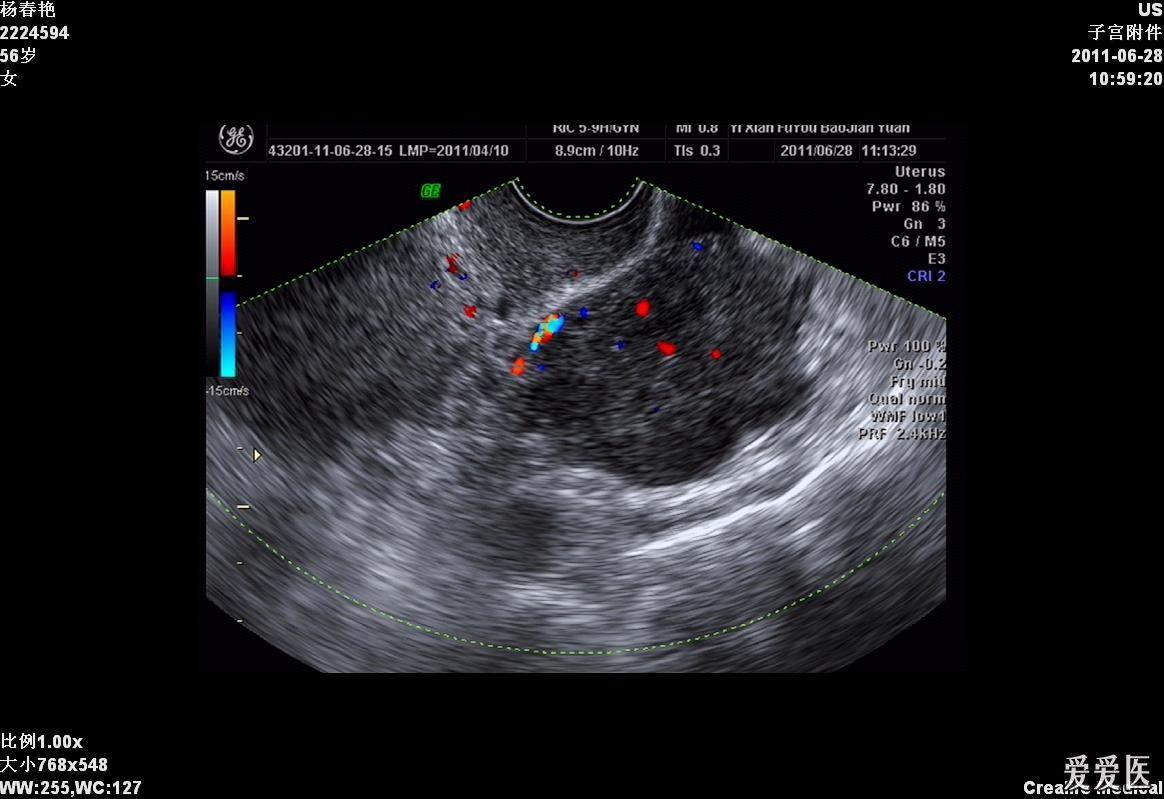

【讨论】盆腔囊性包块 病史资料完整(有病理结果)